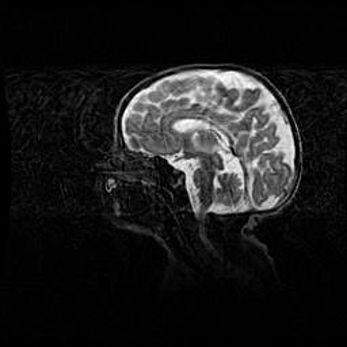

Мальформация Денди-Уокера. Киста задней черепной ямки.

Агенезия мозолистого тела.

Возраст: 2,5 месяца

Вес: 2420 г

Пол: женский

Окружность головы: 37 см

Срок гестации: 32 недели

Мальформация Денди—Уокера — редкий вид патологии ЦНС, представляющий собой врожденный порок развития каудального отдела ствола и червя мозжечка, ведущий к неполному раскрытию срединной (Мажанди) и латеральных (Лушка) апертур IV желудочка мозга. Для этогно синдрома характерна триада симптомов: гипотрофия червя мозжечка и/или полушарий мозжечка, кисты задней черепной ямки, гидроцефалия различной степени. В 70% случаев порок сочетается и с другими аномалиями головного мозга, в частности с агенезией мозолистого тела.